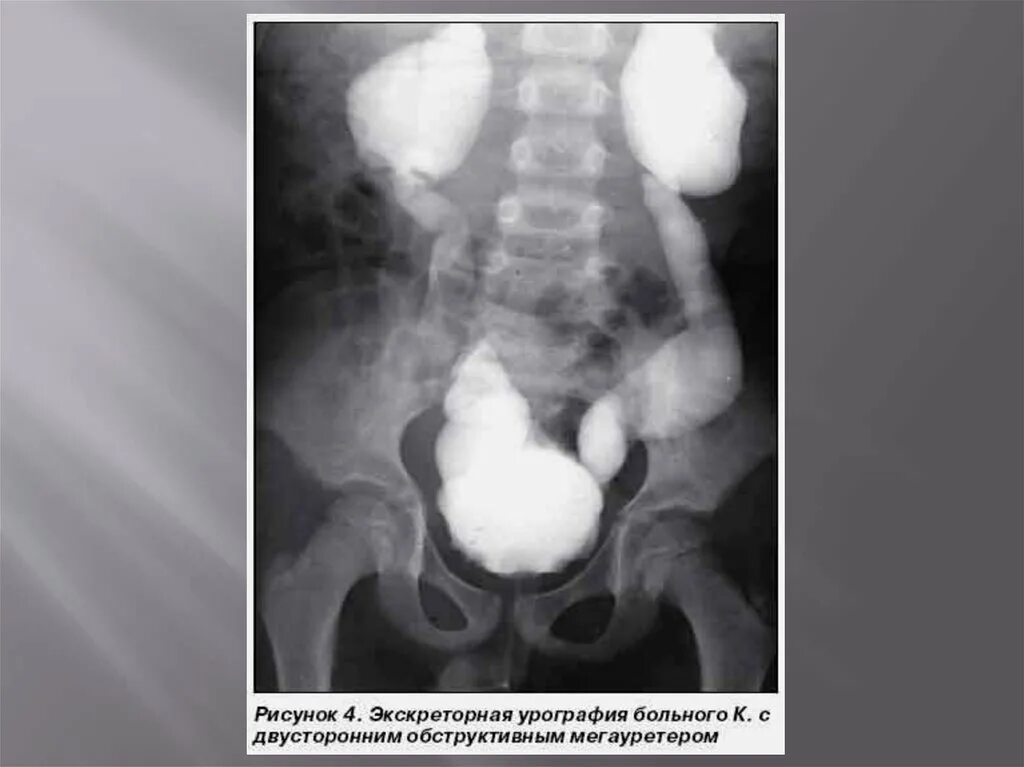

Мегауретер у детей что это